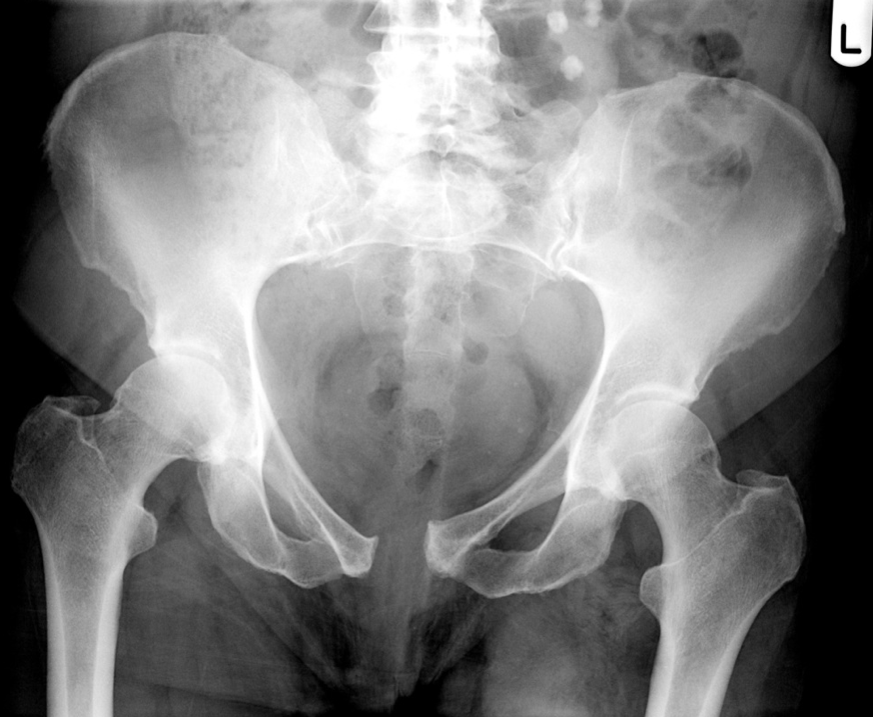

A?

Obturator foramen

B?

Pubic symphysis

C?

Ala (wing) of ilium

D?

Greater trochanter

E?

Lesser trochanter

F?

ASIS

Femoral neck

Ischium

Superior rami of pubis

Inferior rami of pubis

Acetabulum

Femoral head